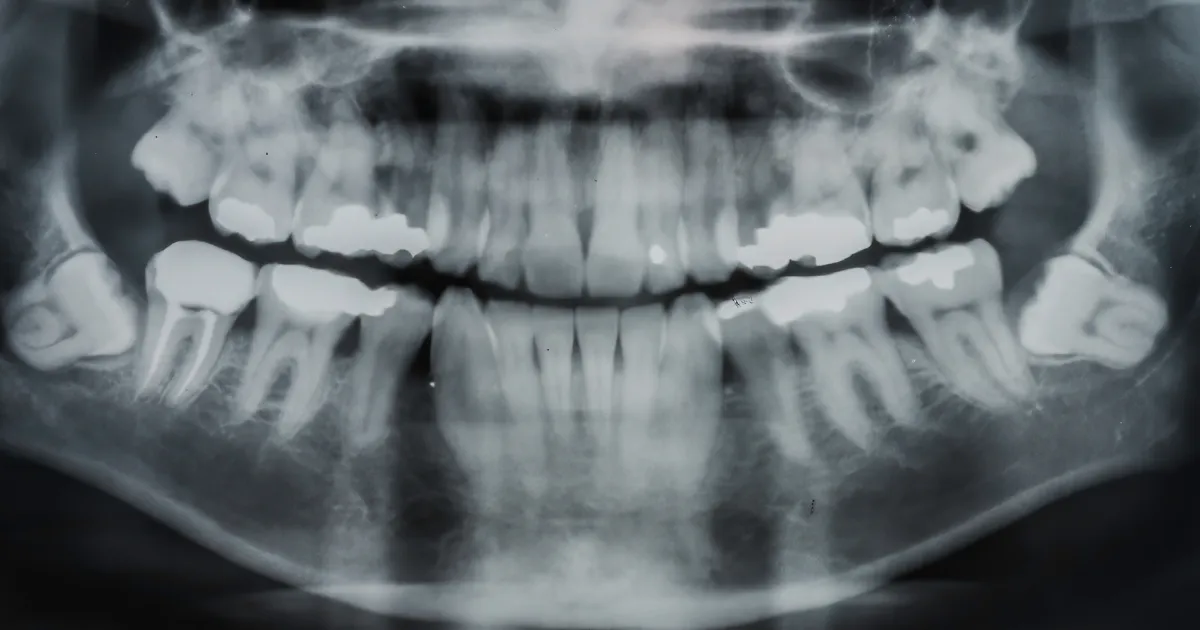

事前にレントゲンやCTスキャンを使い、親知らずの位置や神経との関係を詳細に診断します。

最新設備による正確な診断

歯科ハミール高田88では、CT撮影や最新の3Dスキャナー「iTero」を導入しており、抜歯前の詳細な診断を行います。

これにより、歯の位置や形状、周囲の骨構造を正確に把握し、リスクを最小限に抑えた安全で確実な治療が可能です。

CTによる立体画像解析により、神経や血管の位置も明確にし、難易度の高い親知らずの抜歯にも対応しています。